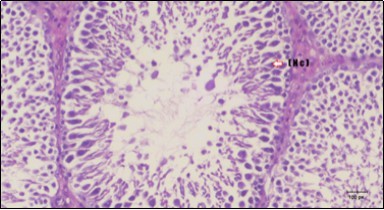

Figure 3.Photomicrogragh of testis section of a control rat showing testicular tissue with seminiferous tubules separated by interstitial tissue with Ledying cells (arrow). Seminiferous tubules with complete spermatogenesis, Sertoli cell (dashed-arrow) and spermatozoa . (H&E) (40X).

Photomicrogragh of testis section of a control rat showing testicular tissue with seminiferous tubules separated by interstitial tissue with Ledying cells (arrow). Seminiferous tubules with complete spermatogenesis, Sertoli cell (dashed-arrow) and spermatozoa . (H&E) (40X).